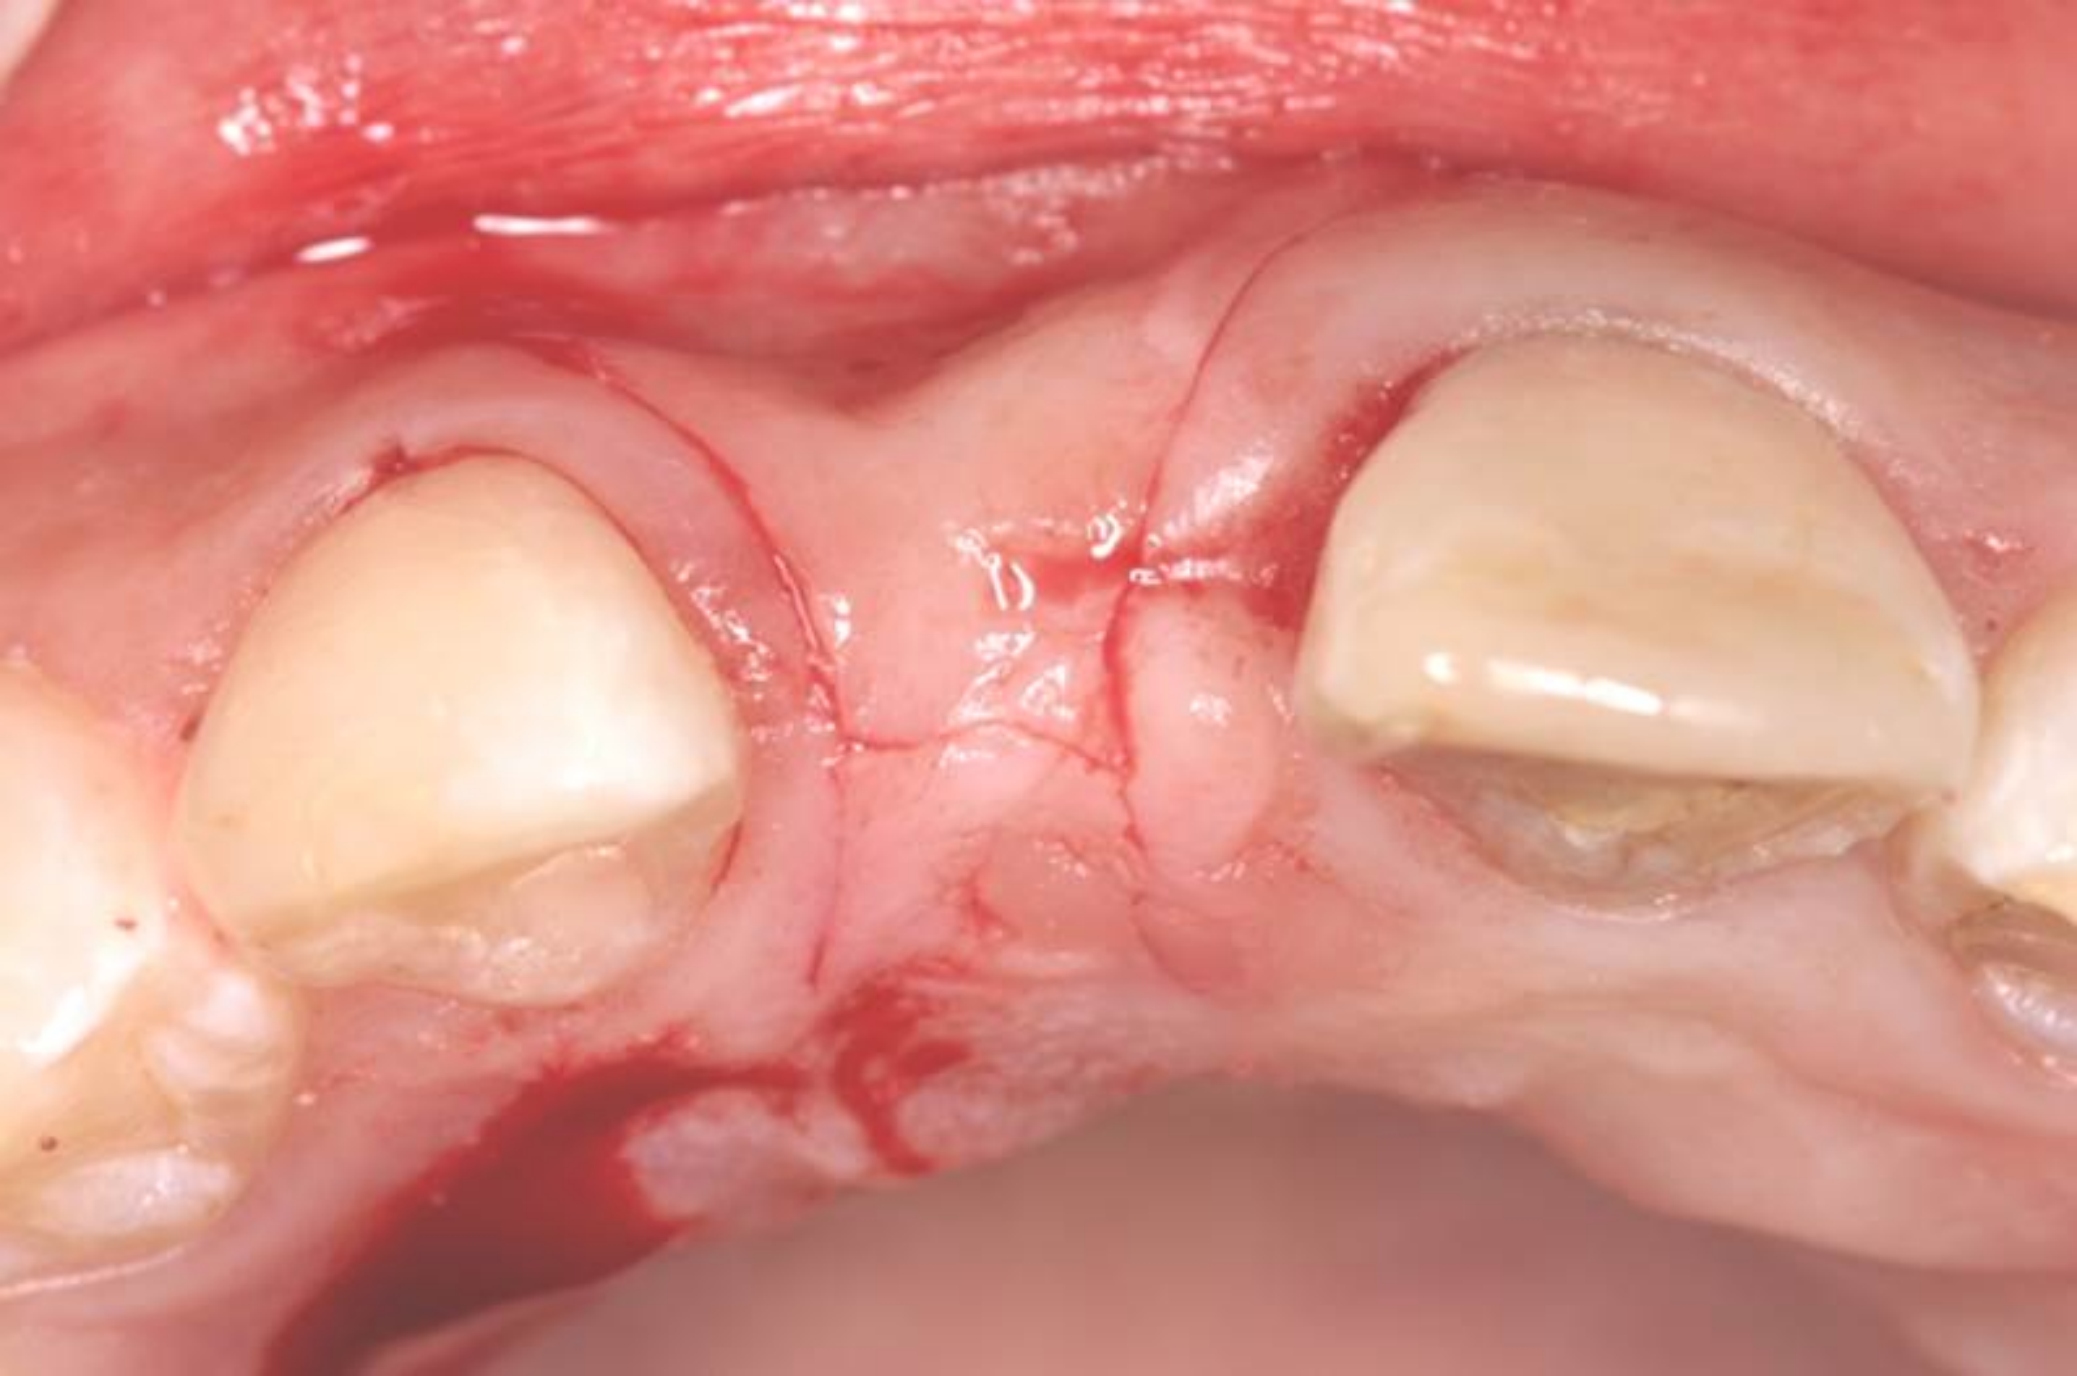

Fig 17. Vertical and horizontal incisions were sutured to attain primary closure.

Figure 17